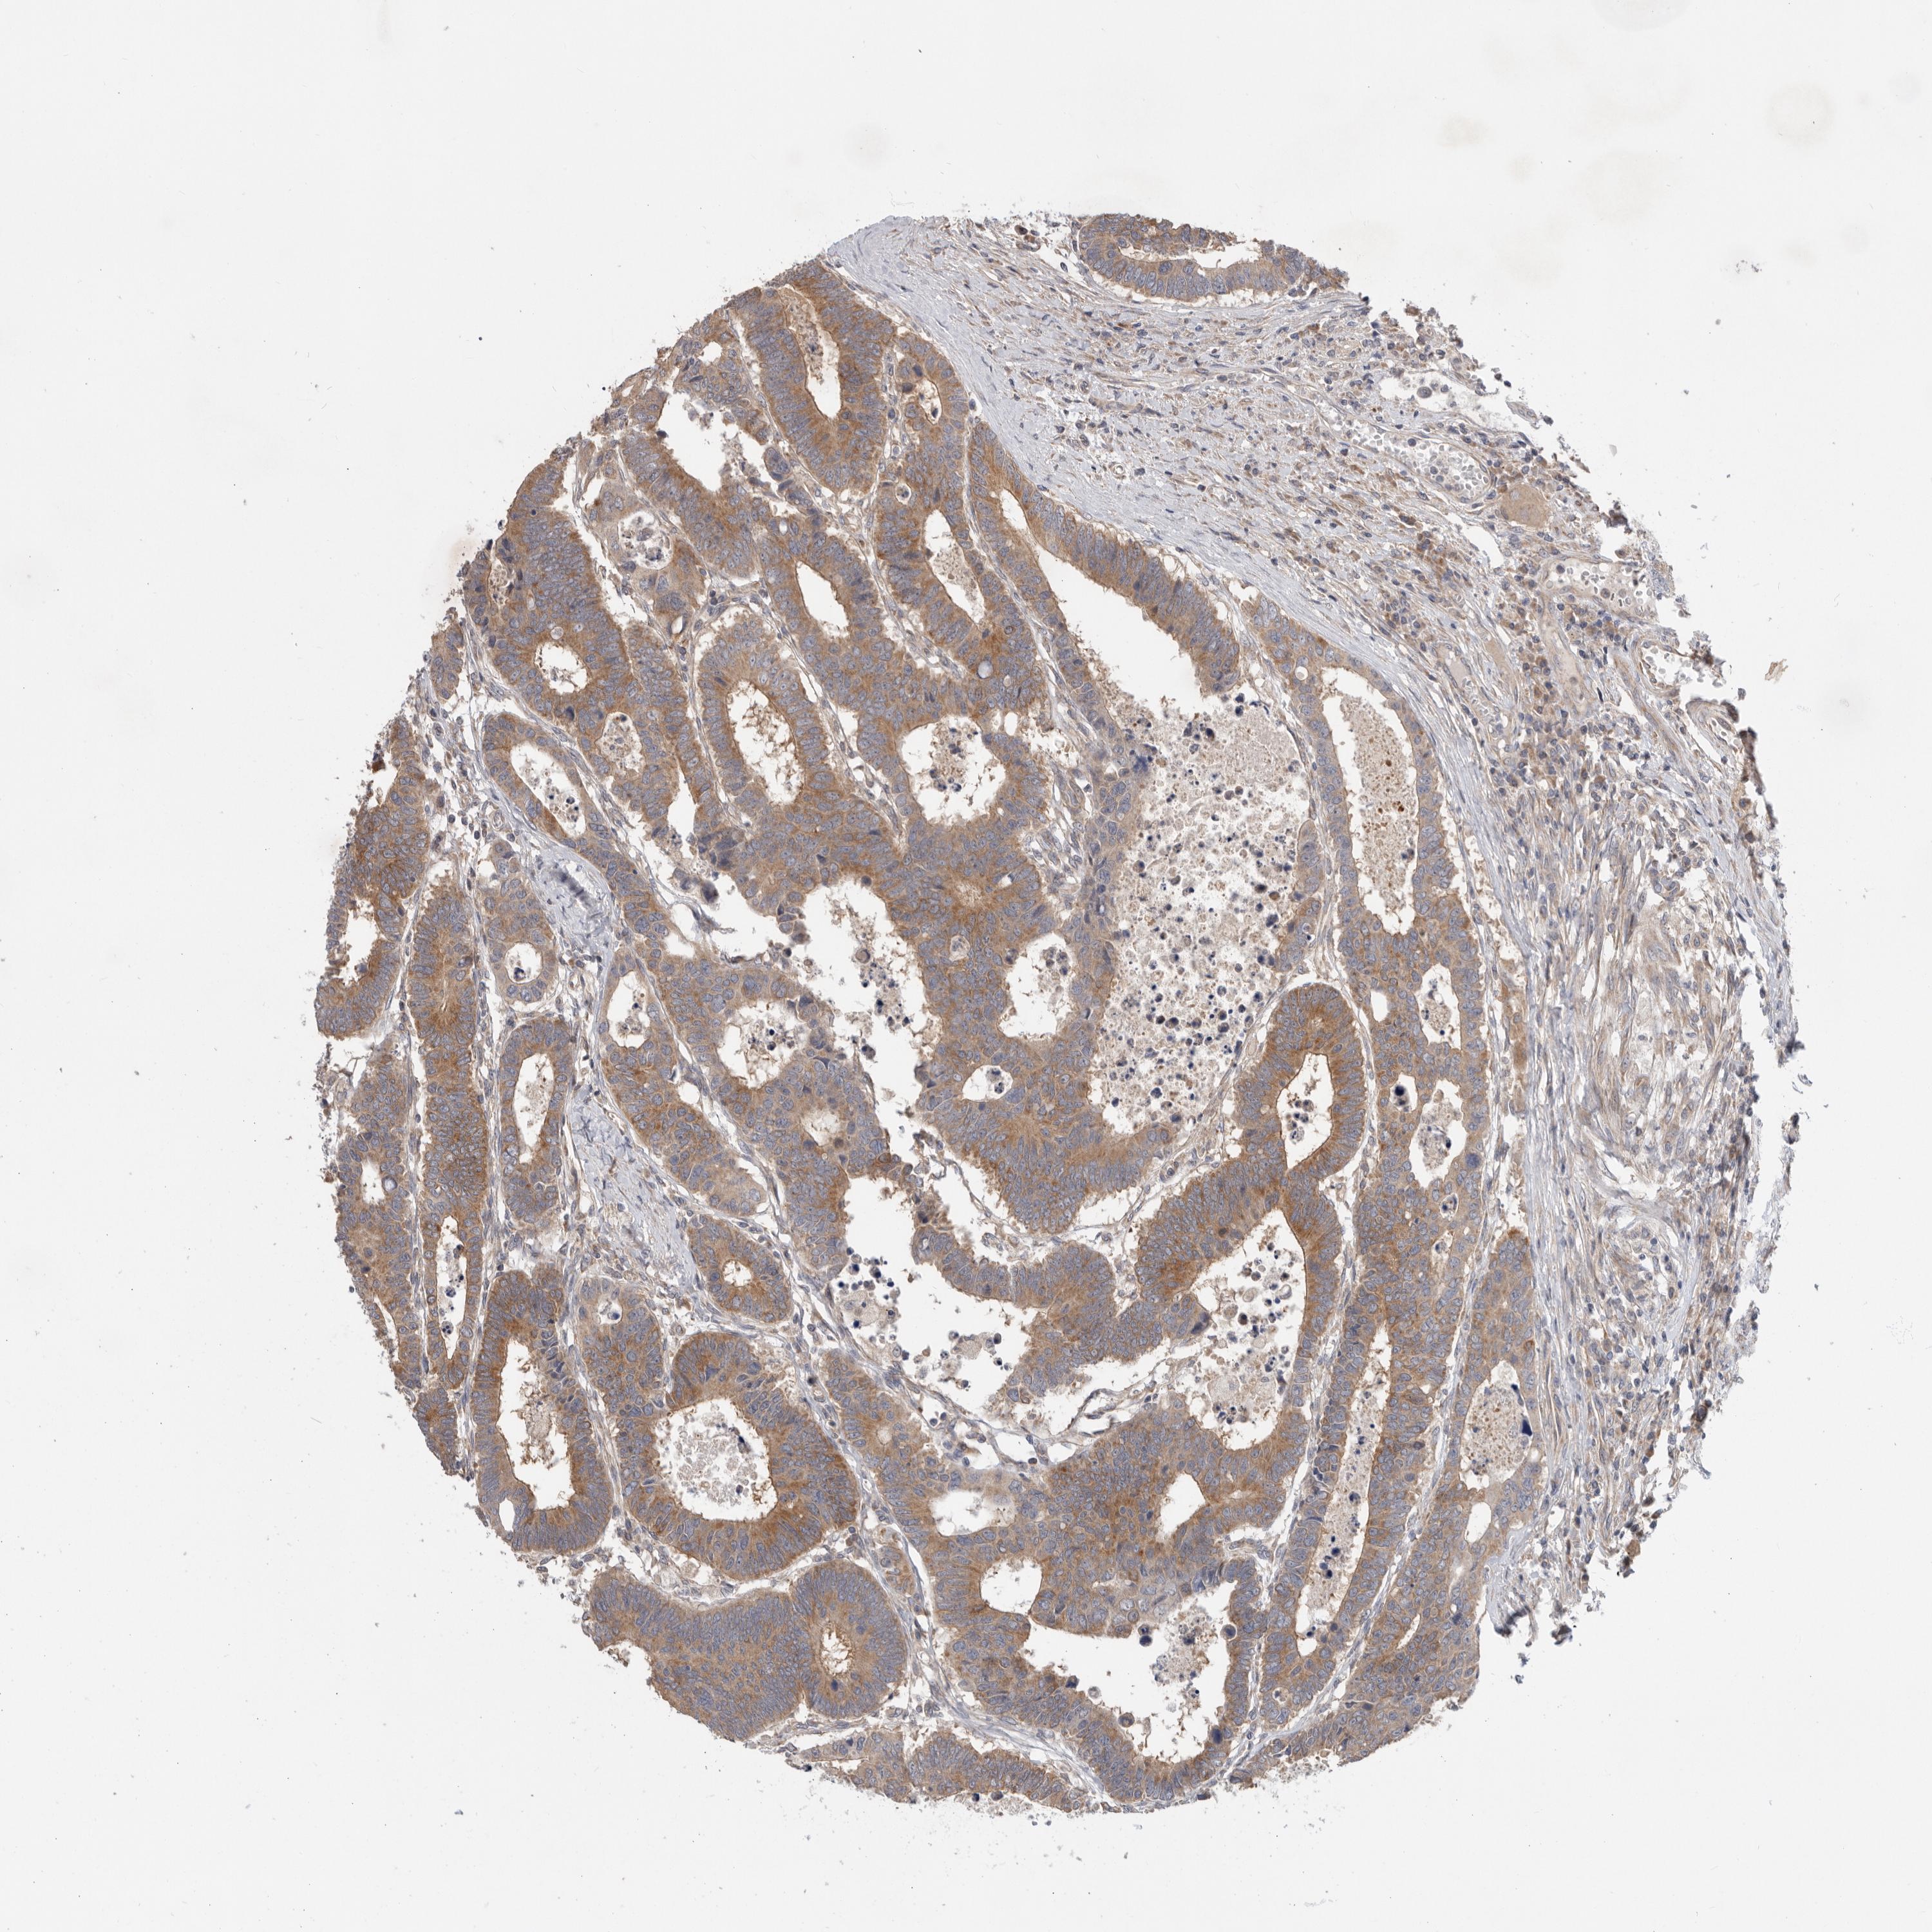

Colorectal cancer

Colon adenocarcinoma